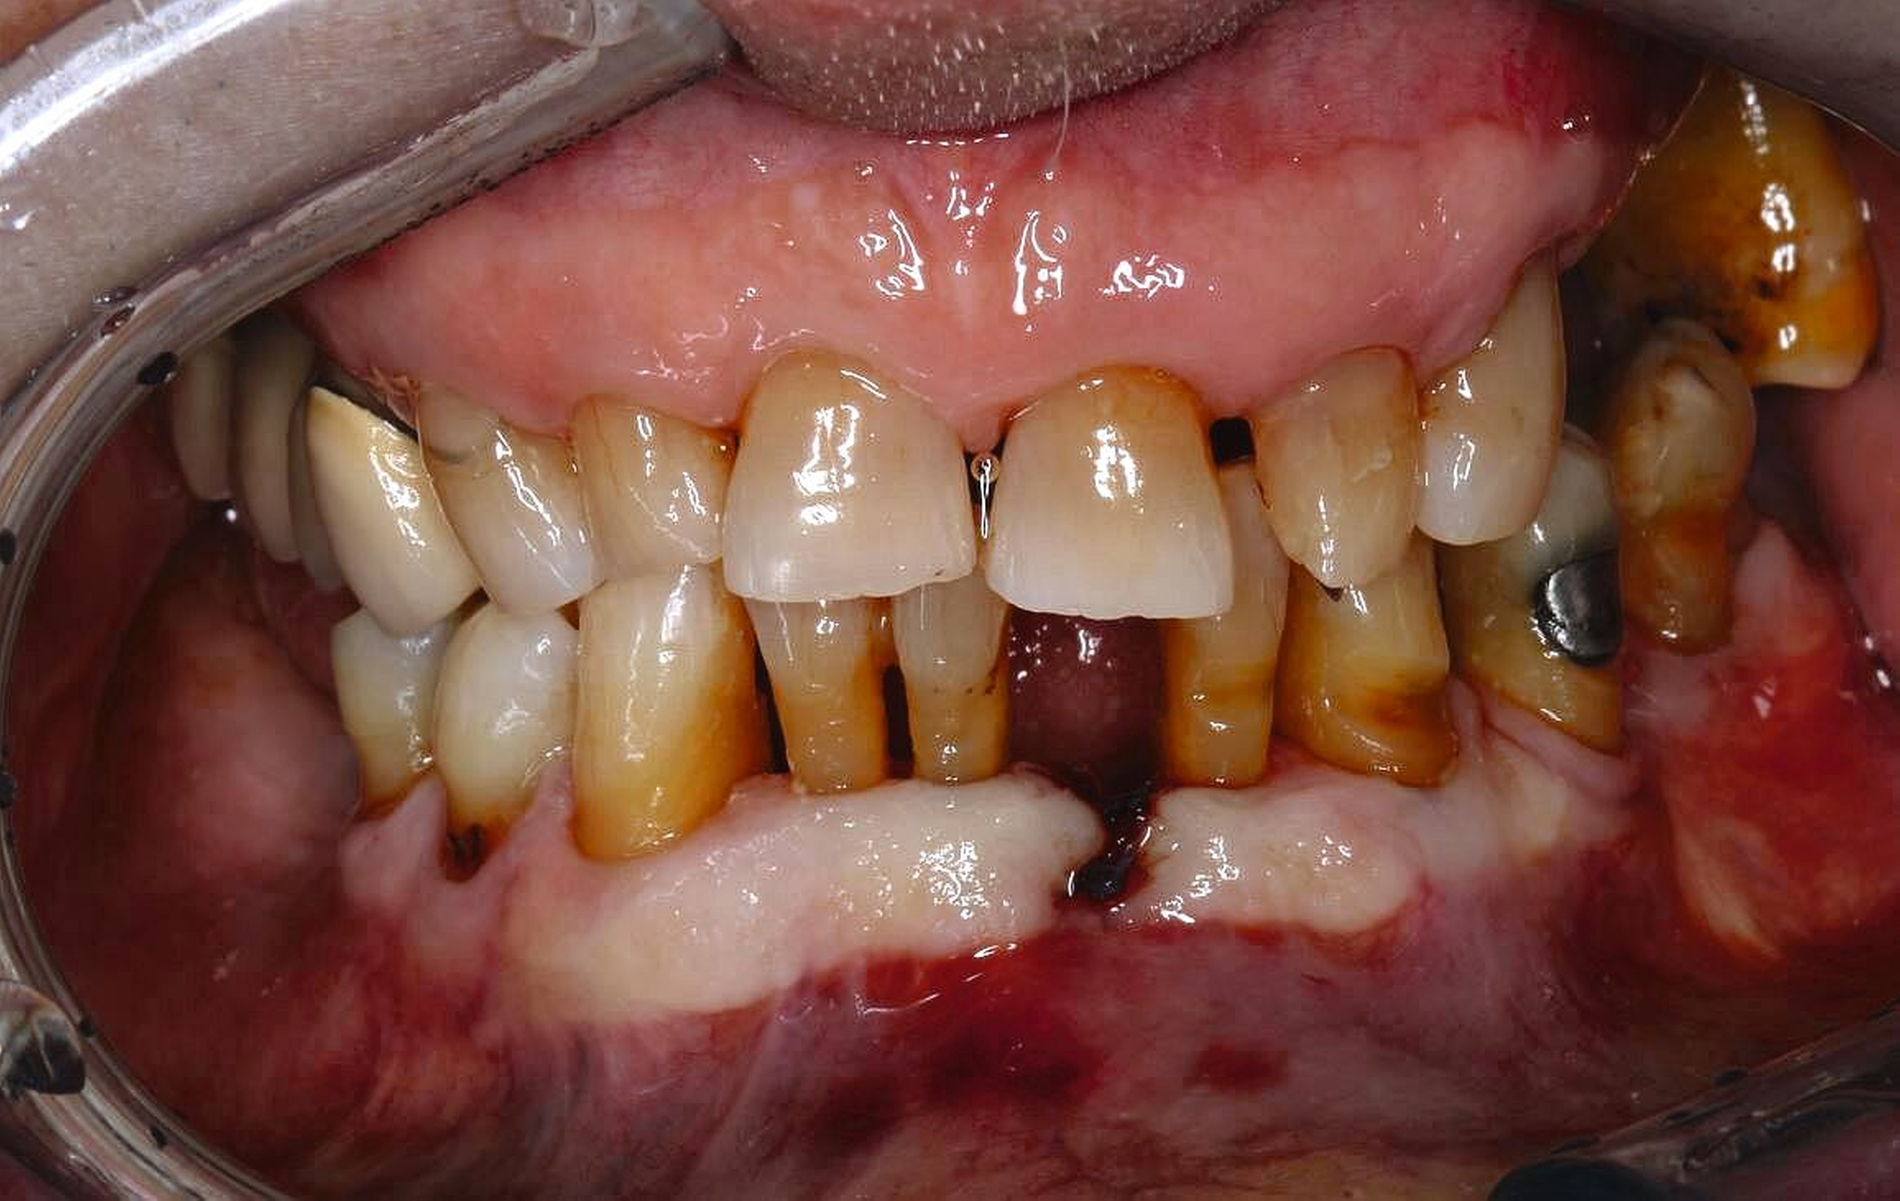

Zahnmedizinische Leitlinien zur zahnmedizinischen Betreuung von geriatrischen und demenziell erkrankten PatientInnen sind aktuell im Entstehungsprozess. Zusätzlich zu den oft komplexen zahnmedizinischen Befunden müssen bei der individuellen Therapieplanung dieser vulnerablen Klientel die Therapiefähigkeit und die Eigenverantwortlichkeit berücksichtigt werden. Dabei ist es weniger das Alter, sondern vielmehr der Zustand der körperlichen und mentalen Funktionsfähigkeit, der den Erfolg zahnmedizinischer Therapien limitiert. Therapien, die bei gesunden Personen jahrelang das Alltagsgeschäft der Zahnmedizin waren, sind bei Personen mit erhöhtem Pflege- und/oder Unterstützungsbedarf eventuell nicht umsetzbar. Gebrechlichkeit (Frailty) ist ein Zustand zwischen guter Gesundheit und Pflegebedürftigkeit im Alter – ein Zwischenstadium, in dem ein vorher fitter älterer Mensch Symptome der Gebrechlichkeit entwickelt und die Gefahr besteht, dass sich sein Zustand verschlechtert. Die geriatrischen Erkrankungen Frailty und auch Demenz sind im Rahmen zahnmedizinischer Behandlungen mit einer reduzierten Kooperations- und Therapiefähigkeit sowie bei der Anfertigung von Zahnersatz mit einer reduzierten Adaptationsfähigkeit assoziiert (Abbildung 3).